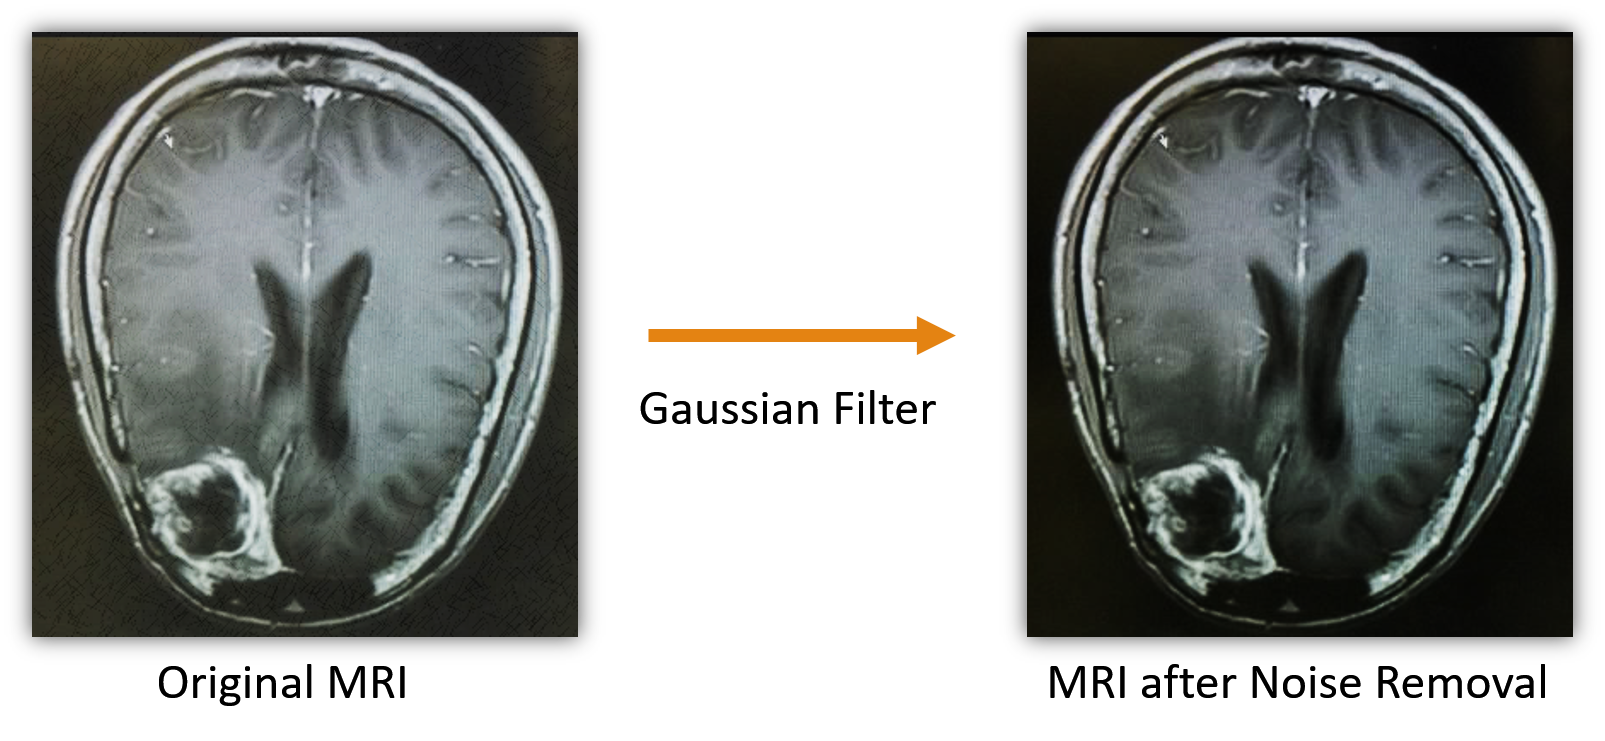

Noise removal: Gaussian filter is a well-known method and is used to smooth a noise by taking the average values surrounding a noise kumar2017noise . In this experiment, the noise removal is performed using a Gaussian filter. Essentially, a Gaussian filter is a low pass filter that is non-uniform. Also, the kernel is symmetric in a Gaussian filter, which can reduce direction bias, if any. Application of a Gaussian filter requires convolution of 2D Gaussian distribution (see Eqn. 2) given an image input. It may be noted that 2D Gaussian distribution is the product of two 1D Gaussian functions (see Eqn. 1). The kernel coefficients are sampled from Eqn. 2. An example showing the noisy image and the same after the removal of noise is shown in Fig. 3.

Figure 3: Example of noisy MR image and the image after noise removal.